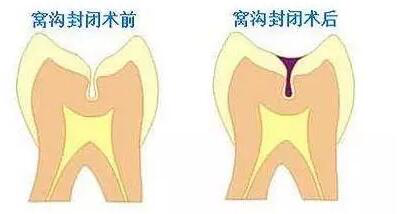

- 别等孩子的恒牙都烂完了,才知道这个预防蛀牙的好办法

- 秒| 想要宝贝的恒牙长得好,关键做好这件事!

- 蛀牙是需要及时补牙的,龋齿没能及时治疗,龋洞会越来越深,影响恒牙的